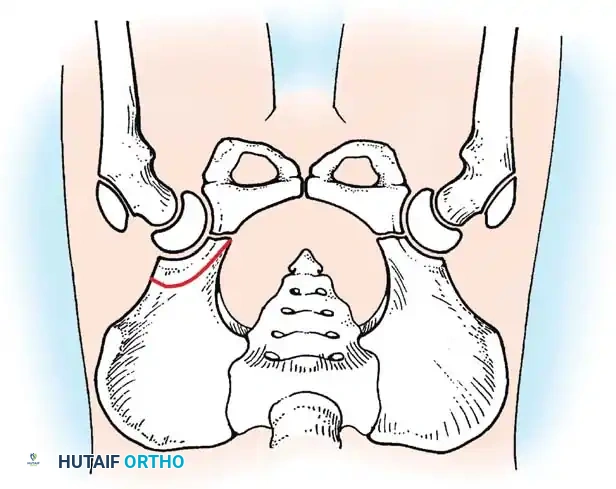

* Hilgenreiner's Line: A horizontal line through the triradiate cartilages.

* Perkins' Line: A vertical line dropped from the lateral margin of the acetabulum, perpendicular to Hilgenreiner's line.

* Shenton's Line: A continuous arc drawn from the medial border of the femoral neck to the superior border of the obturator foramen. Disruption indicates proximal migration.

* Acetabular Index: The angle between Hilgenreiner's line and a line drawn from the triradiate cartilage to the lateral edge of the acetabulum. Normal is <30 degrees in newborns; >35 degrees is highly suspicious for dysplasia.

Radiographic evaluation: Normal hip anatomy (left) versus Dysplastic hip anatomy (right) demonstrating disruption of Shenton's line and an increased acetabular index.